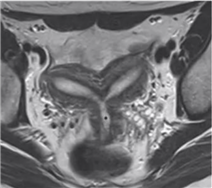

鞍状子宫

又称弓形子宫,双侧副中肾管相当于宫底部分的一小段未能完全融合

外形多正常,有时可见宫底外缘平坦或轻微凹陷,宫底肌层略突向宫腔内

T形子宫

为医源性先天性子宫发育异常,常见于其母亲孕期有服用乙烯雌酚病史者

宫腔形态呈特征性的T形,宫腔边缘不整